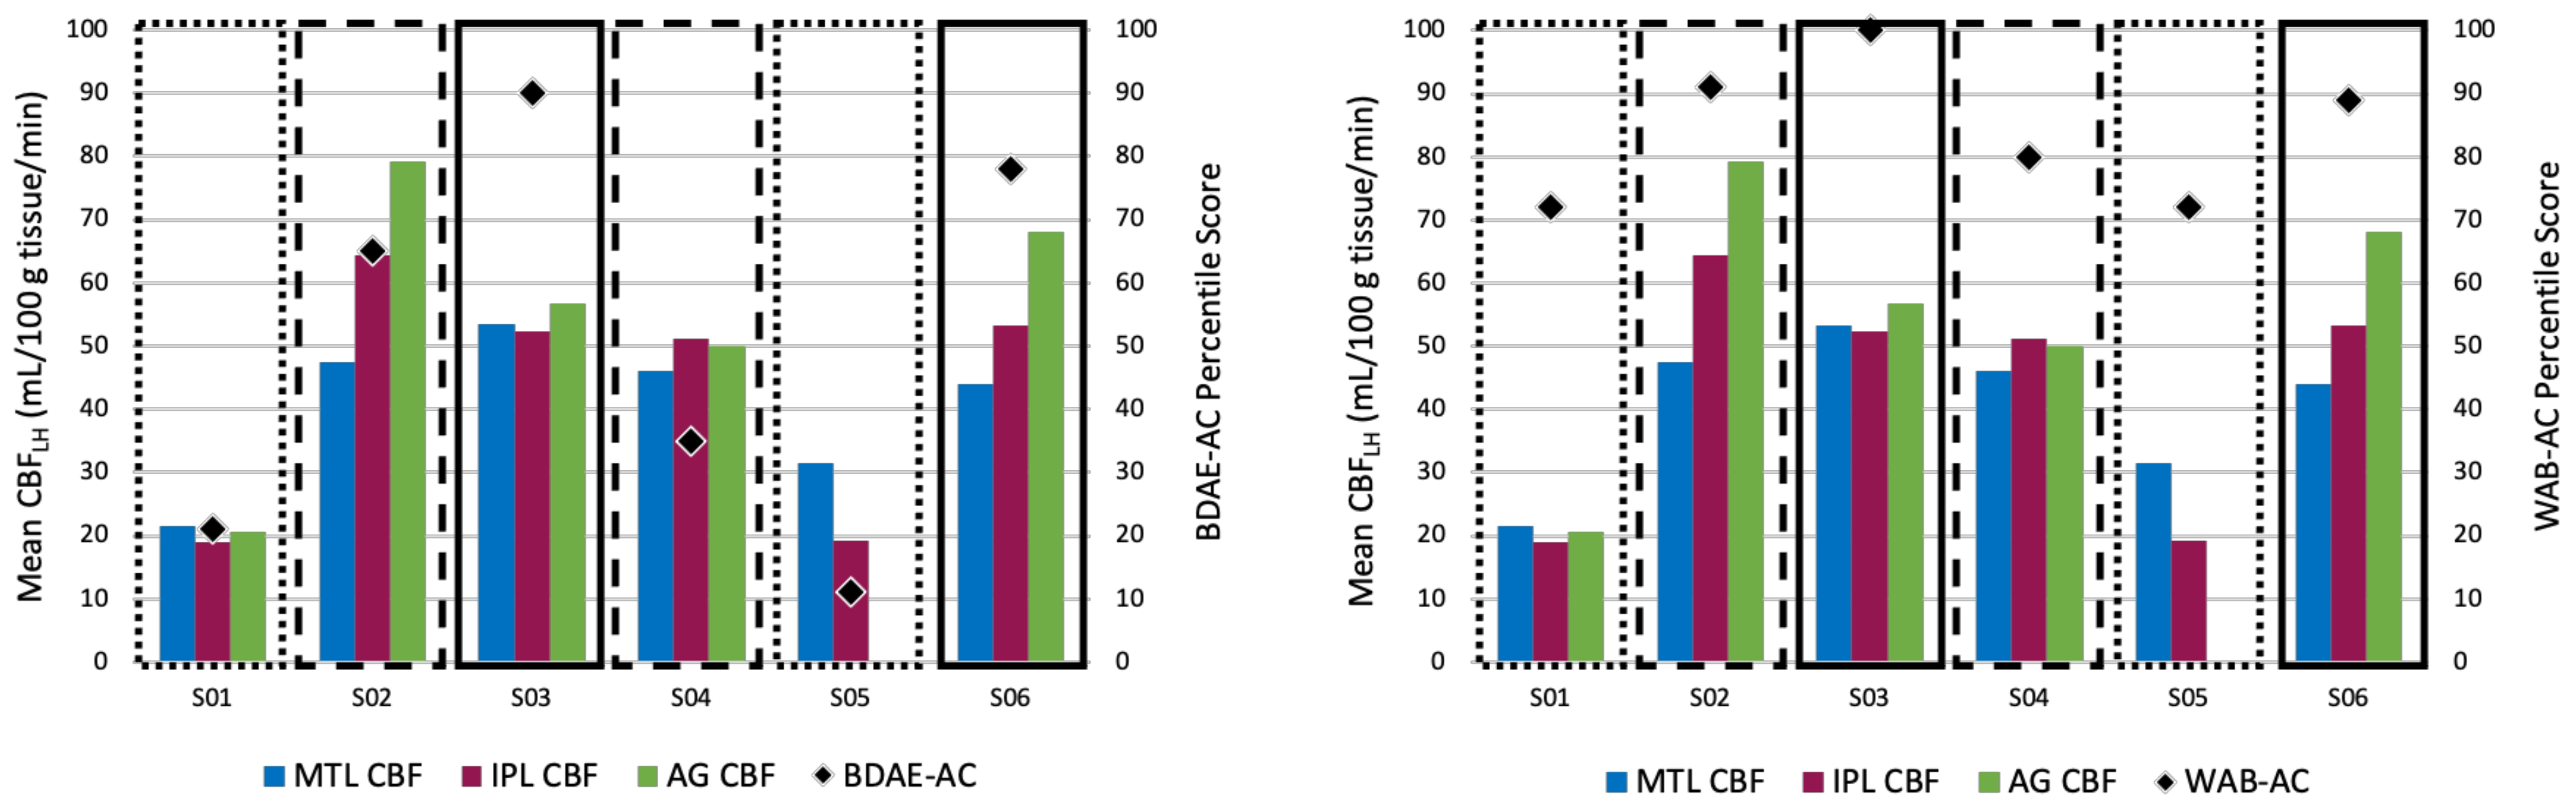

4.5. Identifying Hypoperfused Tissue in Language Regions

4.6. Hypoperfusion and Language Behavior